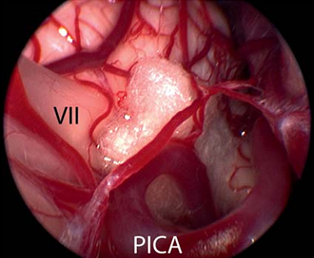

面神经的微血管减压术是治愈面肌痉挛的唯一治疗选择。手术旨在去除出脑干区(REZ)血管对神经的压迫。血管对神经造成压迫是主要病因。手术需全身麻醉。为了观察手术过程中耳蜗的和面部的神经的改变,需要在手术进行过程中对面神经的肌电图(EMG)和听觉诱发电位(auditory evoked potentials)进行监测。使用乙状窦后入路开颅术(retrosigmoidal craniotomy)(figure 3)暴露小脑桥脑角。在随后的手术过程中,尤其注意检查出脑干区的面神经(figure 5),该面神经发源于脑干。内窥镜检查法对于确定血管压迫位置很有效(figure 4,6)。因此,在米兰·(milan)医院把内窥镜检查法作为指导程序。

Figure 4内窥镜图像(使用30°内窥镜拍摄)显示了出脑干区的蜗神经和面神经的临近部位,它们被小脑后下动脉(PICA)环所压迫(与figure 2是同一患者)

Figure 7纤维手术将面神经和血管分离后,在面神经和血管间置入聚四氟乙烯海绵体,达到永久性防止血管压迫。(Ⅶ=面神经;小脑右下动脉(PICA))